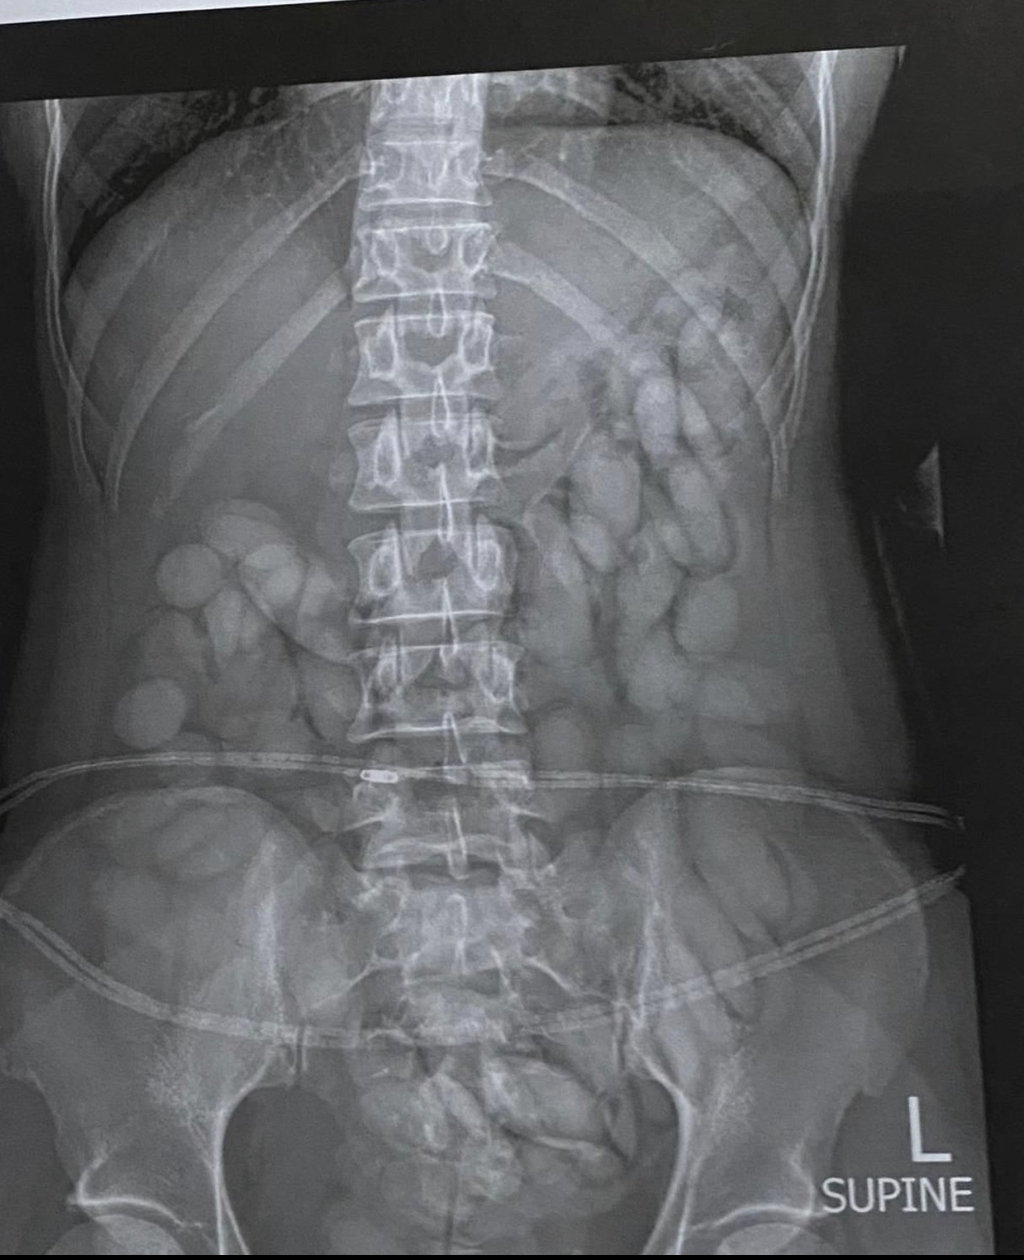

Turns out, the woman was a drug mule who had swallowed 68 “bullets” of cocaine. Yes, you read that right—swallowed them. When she went through security, an X-ray of her stomach showed the whole thing, revealing several foreign objects inside her body.

The x-ray in question that led to the woman's arrest. Credit: South African Police Service

“The team immediately intercepted the drug mule as she was making her way through immigration. She was immediately arrested, taken to a local hospital where a medical X-ray confirmed and detected foreign objects in her stomach." She added, “She has already released more than 60 bullets of suspected cocaine thus far.”